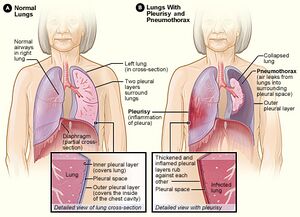

| Figure A shows normal anatomy. Figure B shows lungs with pleurisy in the right lung and a pneumothorax of the left lung. | |

ذاتُ الجَنَب Pleurisy مصطلح عام لالتهاب غشاء الجنب، الذي يبطن داخل الصدر، ويغطي الرئتين. انظر: غشاء الجنب. وجانبا الغشاء رطبان عادة، ويسمحان للرئتين بالتحرك بسهولة على جدار الصدر عندما يتنفس الشخص. وعند التهاب سطْحَي الغشاء، يصبح جافا وخشناً ويحتك بعضه مع بعضه الآخر. وينشط الالتهاب مستقبلات الألم في البطانة الجنبوية داخل الصدر، ويسبب ألمًا حادًا، ويصير أسوأ عند السعال أو التنفس بعمق.

الانصباب الجنبي

تحدث بعض حالات التهاب الجنبة بسبب وجود كميات زائدة من السائل الذي يتراكم في الجوف الجنبي. يطلق على هذه الحالة اسم الانصباب الجنبي. عادة ما يرغم تراكم السائل الطبقتين الجنبيتين على الانفصال لذلك لا تحتك الطبقتان ببعضهما البعض أثناء التنفس. ويؤدي ذلك إلى تخفيف ألم التهاب الجنبة. من الممكن لكمية كبيرة من السائل الزائد أن تدفع الجنبة باتجاه الرئة أو جزء من الرئة مما يؤدي إلى انهيارها. وقد يؤدي ذلك إلى صعوبة في التنفس.

استرواح الصدر

وكما يتراكم السائل في الجوف الجنبي فإنه من الممكن أيضًا تراكم الهواء أو الغاز فيه، يطلق على هذه الحالة اسم استرواح الصدر، تنشأ هذه الحالة من حدوث إصابة حادة في الرئة أو مرض رئوي مثل الانتفاخ، كما أن الإجراءات التي يتم تطبيقها على الرئتين مثل: الجراحة، سحب السائل باستخدام الإبرة، فحص الرئة من الداخل باستخدام ضوء وكاميرا أو التهوية الميكانيكية تسبب أيضًا استرواح الصدر.

العَرَض الأكثر شيوعًا لاسترواح الصدر هو ألم مفاجئ في جانب واحد من الرئة وضيق في التنفس، قد يعرض استرواح الصدر الرئة إلى الضغط مما قد يسبب انهيارها، وإذا كان استرواح الصدر صغيرًا فإنه قد يذهب ويعالج من تلقاء نفسه، أما إذا كان كبيرًا فإن أنبوبًا صدريًا يوضع خلال الجلد وجدار الصدر ليصل إلى الجوف الجنبي لإزالة الهواء منه.